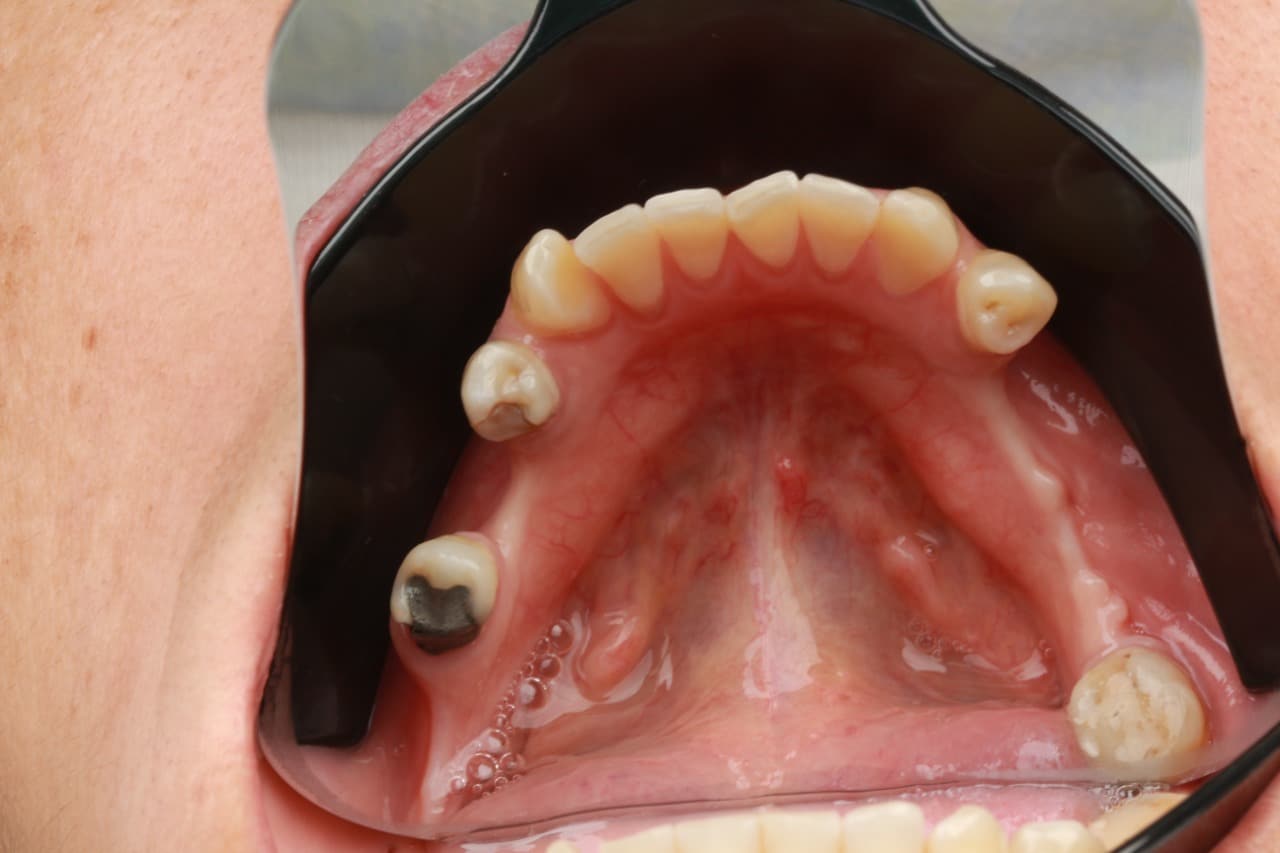

Cirurgia Guiada por Dr. João Marcelo Arcoverde

Adepto à filosofia de trabalho de que menos é mais, Dr. João Marcelo Arcoverde se tornou pioneiro no Brasil ao unir a técnica que permite repor dentes perdidos sem a necessidade de cortes e uso de bisturi convencional que diminuem drasticamente a necessidade de enxertos ósseos.

A Cirurgia Guiada é uma técnica inovadora, cujo implante dentário é feito sem cortes e pontos, portanto gerando maior conforto ao paciente, seja na reposição de um dente, de vários ou de todos.